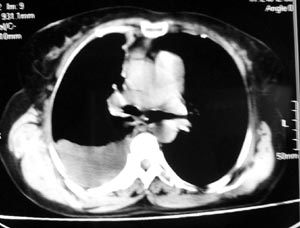

患者女性,52岁,胸闷,咳嗽,活动后气短2个月,加重1周.血常规:wbc10.28,rbc4.62,hgb135,plt267.胸水

常规:李凡他(+).胸水ada:68.1,ldh:303.6.胸水脱落细胞:未查到肿瘤细胞.

双肺纹理增多增粗,右上肺可见纤维条索致密影,右肺门粗浓,右侧胸腔积液,纵隔未见明显肿大淋巴结,

考虑肺部感染?

考虑右肺感染、胸膜增厚、胸腔积液。

图像不是太好,但可以见到下列恶性征象:

1 单侧肺门增大

2 纵隔侧胸膜明显增厚

3 肋胸膜结节影

结合纵隔略宽、单侧胸水首先考虑肺癌。